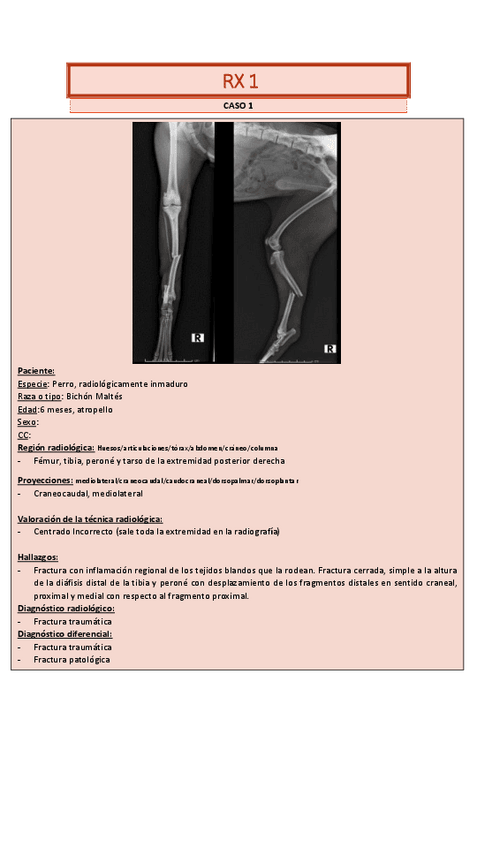

CASOS-RADIOLOGIA-OSEA.pdf